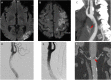

Carotid free-floating thrombus (FFT) is very rarely diagnosed in patients with acute ischemic stroke. It is a real clinical emergency due to the significant risk of death associated with thromboembolic complications. Herein, we present three patients with ischemic stroke caused by carotid FFT after less than 20 days from administration of mRNA vaccine BNT162b1 (Pfizer/BioNTech) for Severe Acute Respiratory Syndrome-CoronaVirus 2 (SARS-CoV-2). To our knowledge, these are the first cases reporting carotid FTT following SARS-CoV-2 vaccination.